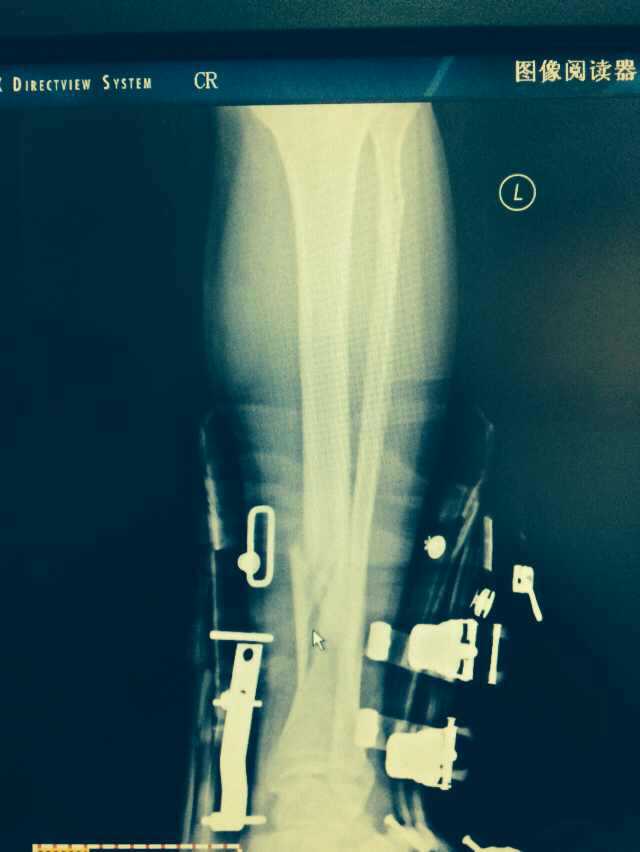

【byb.cn 】(來(lái)源:綜合)2014年12月18日,現(xiàn)年57歲的著名體育評(píng)論員韓喬生,在崇禮云頂滑雪場(chǎng),騎行德國(guó)雪上自行車(chē)的時(shí)候,因速度太快,控制不住,韓喬生為避免沖下路基,與一滑行單板的美女相撞,美女因裝備厚,無(wú)大礙,韓喬生則導(dǎo)致左腿脛骨、腓骨兩外骨折,后已經(jīng)被緊急送往北京的醫(yī)院治療。